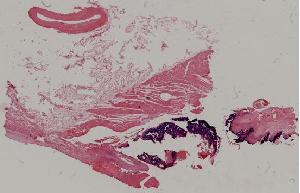

43. Subacute bacterial endocarditis